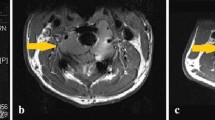

A 17-year-old female presented with cauda equina symptoms. MRI at presentation (a, b), after 8 months on denosumab (c, d) and after 13 months on denosumab (e, f). a Coronal T1-weighted MR image at presentation illustrates a large sacral GCTB, which is iso-intense to muscle on T1. b Sagittal T1 turbo inversion recovery magnitude (TIRM) MR image at presentation illustrates heterogeneous, predominantly high TIRM signal intensity in the tumour with a soft tissue component anteriorly, epidural and sacral foraminal extension. c Coronal T1-weighted MR image after 8 months on denosumab shows decreased signal intensity in the tumour, corresponding to sclerosis. d Sagittal T1 TIRM MR image after 8 months on denosumab shows the tumour has decreased in signal intensity and in size, which is mainly visible in the reduction of the soft tissue component. e The patient reported increased sacral pain after 13 months on denosumab treatment, and an interval MRI was performed. Coronal T1-weighted MR image demonstrates that tumour size and T1 signal intensity remain more or less unchanged. f Sagittal short tau inversion recovery (STIR) MR image after 13 months on denosumab demonstrates a marked increase in signal intensity of the tumour on the fluid-sensitive sequence, indicative of tumour reactivation. The patient was subsequently found to be pregnant and denosumab therapy was interrupted. Re-biopsy performed 3 months postpartum revealed numerous osteoclastic giant cells supporting the diagnosis of GCTB reactivation. Denosumab therapy was subsequently recommenced with a good clinical response and stable disease on treatment (2 year follow-up to date)

Upregulation of GCTB while on denosumab therapy may occur in pregnancy due to hormonal influences causing a rapid increase in tumour growth and activity [38, 39]. This may be seen as increased signal on fat-suppressed fluid-sensitive MR sequences, whereas T1-weighted signal may remain static (Fig. 7). Two case reports of GCTB recurrence during pregnancy in the capitate and in the spine described rapid expansion of the tumour during pregnancy [38, 39]. Females on denosumab should be advised to avoid pregnancy and take appropriate contraceptive precautions as there is evidence that denosumab is associated with increased stillbirth and decreased body weight gain, growth and development in studies of animal infants exposed in utero [40, 41]. Skeletal effects observed in infant monkeys exposed in utero are consistent with the anticipated pharmacological activity of denosumab with inhibition of bone resorption and impaired bone remodelling during skeletal development resulting in an osteoclast-poor osteopetrotic like skeletal phenotype at birth and in the early postnatal period [42].

A 17-year-old female with a sacral GCTB (same patient as Fig. 7). PET-CT at baseline (a), after 8 weeks on denosumab (b) and after 16 weeks on denosumab (c). a Coronal fused PET-CT at baseline shows marked 18F-FDG uptake in the sacral GCTB which had an SUVmax of 16.3. No metastases were present. b Coronal fused PET-CT after 8 weeks on treatment demonstrates that the SUVmax had decreased to 4.4. c Coronal fused PET-CT after 16 weeks on denosumab demonstrates a complete response